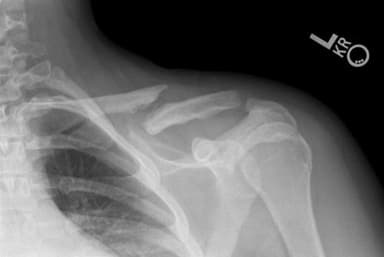

- Gãy Xương Đòn Đeo Đai Số 8 Bao Lâu thì có thể Tháo được?